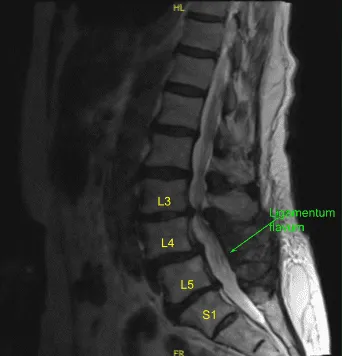

Un paciente acudió a una clínica de neurocirugía con signos y síntomas de estenosis lumbar con claudicación neurogénica y caída del pie derecho. Las imágenes mostraron estenosis severa en L4-5 central y L5-S1 en el izquierdo. Se recomendó cirugía para descomprimir la columna lumbar.

La laminectomía se realizó con un taladro eléctrico de alta velocidad bajo riego estéril continuo, exponiendo un ligamento flavo hipertrofiado que se resecó a partes con Kerrisonrongeurs, protegiendo cuidadosamente la duramadre con elevador Woodson, y se retiró con el Penfield #4.